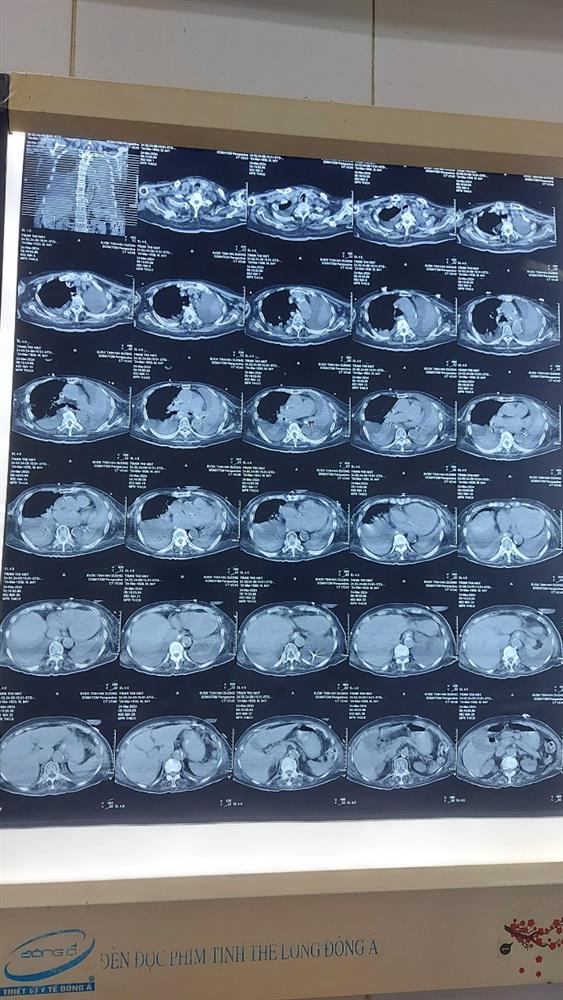

Bệnh nhân nữ 94 tuổi di chứng tai biến mạch não, viêm phổi ứ đọng, suy tim được đặt ống NKQ thở máy tại khoa HSTC và chống độc - BVĐK tỉnh Hải Dương. Sau điều trị 1 tuần điều trị kháng sinh bệnh nhân chụp lại phổi có tràn dịch màng phổi 2 bên, xẹp phổi thụ động thùy dưới 2 bên. Bệnh nhân đã được hội chẩn khoa hô hấp, được các bác sĩ khoa hô hấp chọc dịch dưới siêu âm màng phổi bên trái, hút ra 500ml dịch. Sau đó tiến hành nội soi phế quản và bơm rửa phế quản 2 bên. Sau 01 tiếng thực hiện thủ thuật cấp cứu của ekip bác sĩ Hô hấp và bác sĩ Hồi sức tích cực, 2 lá phổi bệnh nhân đã được hồi sinh, tình trạng hô hấp được cải thiện tốt.

Hình ảnh phổi trước khi can thiệp

Hình ảnh phổi sau khi can thiệp